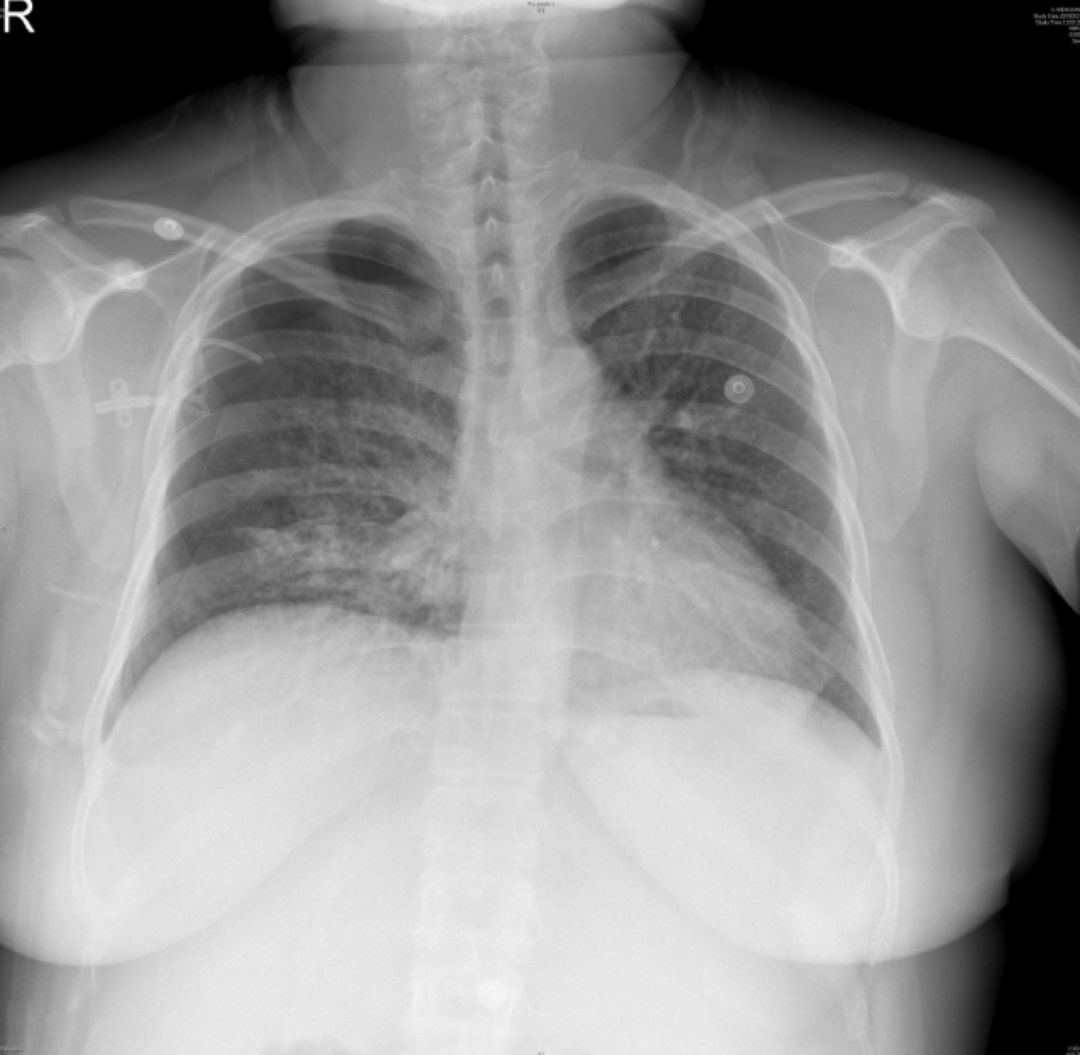

2019-5-13我院胸片

患者青年女性,因「咳嗽、咳痰、咯血半月余,胸痛8天」入院,急性起病,逐渐加重,胸部CT提示右侧气胸,双肺相对弥漫分布的气囊与结节,沿气管血管束分布,右下肺实变。肺部弥漫性囊泡样疾病,需要考虑肺淋巴管平滑肌瘤病(LAM)、BHD综合征、肺朗格汉斯组织细胞增生症(PLCH)、淋巴细胞性间质性肺炎(LIP)、感染性疾病如耶氏肺孢子菌肺炎(PCP)等疾病。LAM一般常见于育龄期女性,影像学以弥漫均匀分布的薄壁囊泡为主要表现,此例患者为年轻女性,肺部多发囊泡,需要考虑LAM,但囊泡不是薄壁,分布不均匀,形状不规则,不符合LAM的典型表现。PLCH一般多见于吸烟患者,影像学以奇形怪状的沿支气管血管束分布的囊泡样改变为特点,吸烟患者一般以上叶及中叶病变为主,不累及肋膈角,多系统病变患者可以累及肋膈角,本例需考虑PLCH可能。BHD综合征肺部表现为多发薄壁囊肿,形状不规则,多于基底部、外周、沿纵隔分布,其他系统表现可合并皮疹、肾肿瘤等,可有家族史,本例患者无BHD家族史,需进一步排查其他器官有无病变。LIP常有肺部多发囊泡改变,一般合并自身免疫性疾病,该患者需进一步完善自身抗体等风湿免疫相关指标,协助诊断。此外,还需考虑PCP、金葡菌感染等感染性疾病。PCP多见于免疫抑制宿主,可以有多发性肺气囊的表现,该患者无发热,无免疫抑制病史,目*考前**虑可能性不大。

5-16胸片

本例患者的胸部CT主要表现为两肺相对弥漫分布的怪异的气囊和结节,气囊为薄壁,以中上肺分布为主,沿支气管血管束分布,符合LCH细胞沿支气管分布的特点,并且有可能会引起支气管阻塞,类似活瓣样的作用,因此囊腔的形状怪异。胸腔镜术后的CT表现,可能是局部阻塞牵拉引起疱的加重,也可能是胸膜粘连后局限性的气胸的表现。